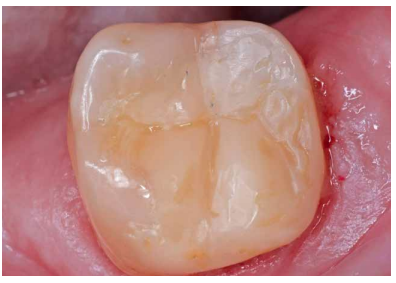

La paciente no presentaba antecedentes médicos de interés. En la exploración clínica (Figura 1) se observó que el 3.7 presentaba una lesión cariosa extensa, correspondiendo a un valor ICDAS 6, y una restauración oclusal previa de composite. En la exploración radiográfica (Figura 2) no se apreciaba banda de dentina entre la lesión cariosa y la cámara pulpar. Por tanto, según la clasificación clínico-radiográfica del International Caries Classification and Management System (ICCMS®) 4 se considera una lesión de caries severa. Presentaba un ligero ensanchamiento del espacio del ligamento periodontal en la raíz mesial y lesión apical. Se realizaron las pruebas de diagnóstico pulpar y periapical pertinentes (Tabla 1). El diagnóstico pulpar fue pulpitis irreversible sintomática y el diagnóstico periapical fue periodontitis apical sintomática.

Se continuó con la remoción no selectiva de la caries y de la restauración previa con fresas redondas de turbina y contraángulo (Figura 3). Posteriormente, se expuso la pulpa en la zona más cercana a la lesión en una extensión de unos 2-3 mm con una fresa estéril redonda de diamante montada en turbina con abundante refrigeración. Se observó la pulpa y la sangre era roja brillante (Figura 4). Se controló el sangrado con una bolita de algodón embebida en hipoclorito de sodio 3% que se aplicó durante 2 minutos (Figura 5).